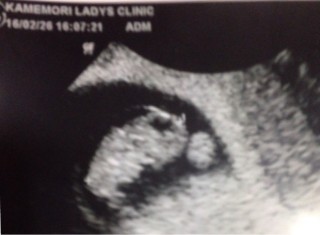

今日婦人科行ったら! まだ確認出来ないかもしれないと言われたたが、いざ内診すると確認出来たので良かった??(*´?`*)??? エコー写真の見方がまだ良く分かりませんヽ(;▽;)ノ

2回目の診察で16mm近くまで成長。初期から出血がありますが成長しててくれてよかった。1週間後心拍が確認できると言われホッとしました。